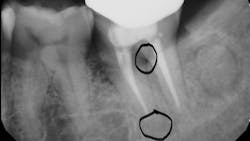

Root fracture is a common source of pain after root canal treatment and is of particular concern since it may be hard to diagnose (figure 1).5 Although new technologies such as three-dimensional imaging and microscopes have increased diagnostic ability, vertical fractures can still be hard to ascertain. Isolated periodontal pockets and a history of sharp pain that progresses to a dull throbbing pain upon mastication/palpation are common signs of fracture. Other common risk factors for fracture include: the lower second molar (most likely tooth to fracture), parafunctional habits including clenching/bruxism, large amalgam restorations, thermal injury, psychological stress, teeth with existing erosion, abrasion, and/or abfraction. A fractured tooth may need to be extracted to alleviate symptoms of pain (figure 2).